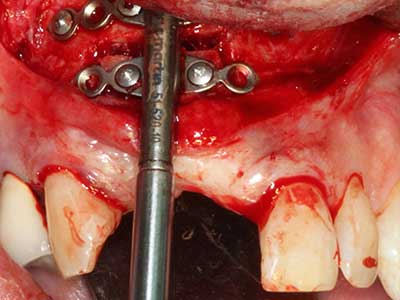

Indication: Apical resection

When surgical procedures are performed on bone in the immediate vicinity of sensitive structures such as blood vessels or nerves, rotary instruments pose a significant risk of iatrogenic injury. Piezoelectric devices can be helpful for preparation of bone covers and removal of hard tissue close to nerves, particularly for exposure of nerves after iatrogenic injury but also during nerve lateralization for resective and reconstructive procedures or implant placement (Fig. 17-20). Light contact between the piezotip and the nerve does not generally result in damage but proceeding incautiously with saw-like motions or attachments where a residual bone substrate remains may cause temporary or even permanent nerve damage. However, the risk of damage is considered to be substantially lower than when using saws or milling instruments (Pereira, Gealh et al. 2014).